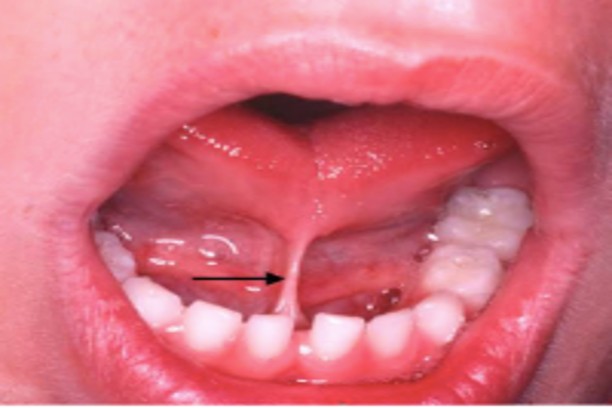

Frenectomy

Corrects lip or tongue tie to improve function

Tongue tie removal

Releases restricted tongue movement to improve speech and feeding.